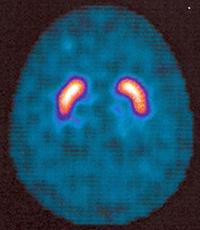

Was ist ein DaTSCAN?

Ein DaTSCAN ist eine Hirnszintigraphie, genauer: eine Dopamin-Rezeptor-Szintigraphie. Diese Untersuchung wird durchgeführt zum Nachweis oder Ausschluß eines Morbus Parkinson. Bei Parkinson-Syndromen und einigen Demenz-Erkrankungen gehen Nervenzellen in der sog. Substantia nigra im Mittelhirn zugrunde (Degeneration dopaminerger Nervenzellen). Die bildliche Darstellung der Substantia nigra ermöglicht eine exakte Diagnosestellung und damit gezielte medikamentöse Therapie.

Hirn SPECT mit unauffälligem Speichermuster. Kein Anhalt für einen Morbus Parkinson.

Zur Vorbereitung auf die Untersuchung erhalten Sie bei uns zunächst Irenat-Tropfen, um eine Radioaktivitätsaufnahme in die Schilddrüse zu blockieren. Einige Zeit danach wird eine mit Jod-123 markierte Substanz in eine Armvene injiziert, die sich im Bereich des Mittelhirns/der Substantia nigra anreichert. Nach drei Stunden werden Aufnahmen des Schädels angefertigt, wobei die Gammakamera um den Kopf kreist. Die Untersuchung dauert etwa 45 Minuten.